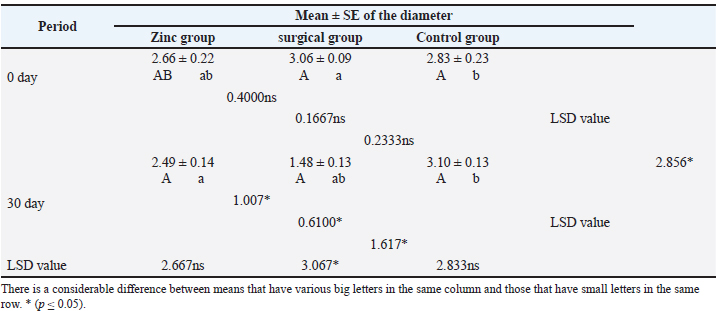

Assessment of the testicular diameterTable 2 shows the mean estimation of testicular diameters. The values of testicular diameter were dramatically (p ≤ 0.05) reduced at day 30 in the surgical group (1.48 ± 0.13) compared with the zinc gluconate group (2.49 ± 0.14) and the control group (3.10 ± 0.13) at the same period. Table 2. Testicular diameter of dogs at day 30th of the study.

Evaluation of testosterone levelsThe baseline serum testosterone concentration (Table 3) was significantly (p ≤ 0.05) declined in animals of the surgical group (1.17 ± 0.26) at day 30 than in the zinc gluconate group (2.55 ± 0.23) and control group (3.53 ± 0.28) at the same time. Conversely, there was a significant (p ≤ 0.05) decline in testosterone levels in the zinc gluconate group compared with the control group. Table 3. Evaluation of testosterone levels (ng/ml) in the treated and control groups.